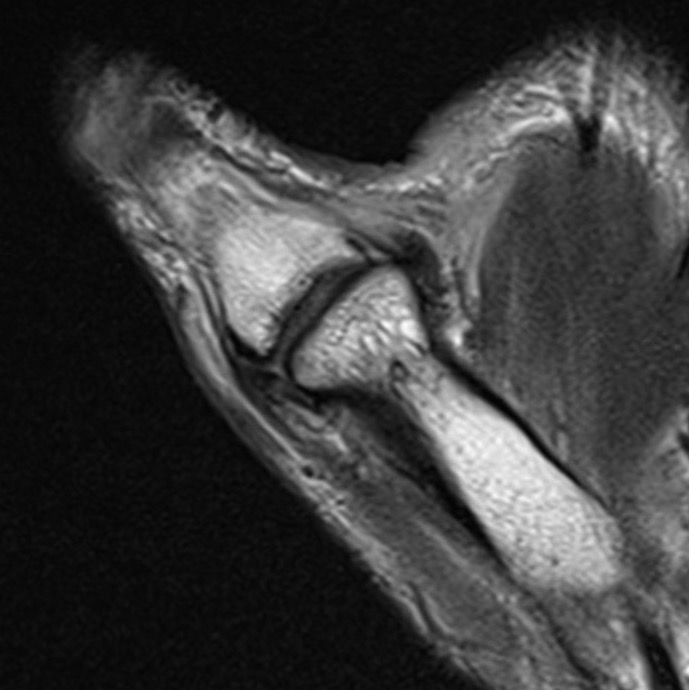

Anatomy

A. Undisplaced

![]()

Distal tear of ulna collateral ligament on coronal MRI